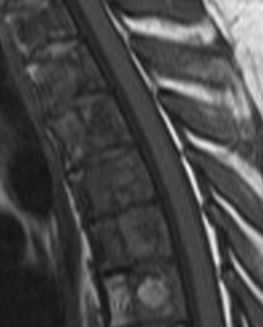

(Слева) Сагиттальный срез, Т2-ВИ, 15-летний пациент: жировая перестройка костного мозга, ограниченная зоной вокруг центральных дренирующих вен каждого позвонка. Остальная часть тел позвонков заполнена красным костным мозгом. Подобная МР-картина типична для пациентов молодого возраста.

(Справа) На сагиттальном Т1-ВИ 50-летнего пациента определяется смешанная картина «ткани в горошек», характеризующаяся перемежающимися друг с другом участками красного и желтого костного мозга. Жировой костный мозг обычно локализуется вокруг дренирующих вен и вблизи замыкательных пластинок. Красный костный мозг характеризуется аналогичной или несколько повышенной по сравнению с мышцами интенсивностью сигнала.

(Слева) На сагиттальном Т1-ВИ 85-летнего пациента определяется практически полная жировая перестройка костного мозга тел позвонков, на фоне которой видны лишь небольшие фокусы эритропоэтического костного мозга. Красный мозг с возрастом подвергается инволюции, однако небольшие его очаги в позвонках, если пациент ранее не получал лучевую терапию, сохраняются всегда.

(Справа) Сагиттальный срез, Т1-ВИ: выраженная разница в интенсивности сигнала между нормальным желтым костным мозгом, изменениями костного мозга на фоне лучевой терапии и опухолевой инфильтрацией костного мозга.

(Справа) На сагиттальном Т1-ВИ 50-летнего пациента определяется смешанная картина «ткани в горошек», характеризующаяся перемежающимися друг с другом участками красного и желтого костного мозга. Жировой костный мозг обычно локализуется вокруг дренирующих вен и вблизи замыкательных пластинок. Красный костный мозг характеризуется аналогичной или несколько повышенной по сравнению с мышцами интенсивностью сигнала. (Слева) На сагиттальном Т1-ВИ 85-летнего пациента определяется практически полная жировая перестройка костного мозга тел позвонков, на фоне которой видны лишь небольшие фокусы эритропоэтического костного мозга. Красный мозг с возрастом подвергается инволюции, однако небольшие его очаги в позвонках, если пациент ранее не получал лучевую терапию, сохраняются всегда.